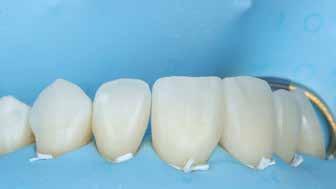

A cikkünkben bemutatásra kerülő eset ellátása során preparációt héjak készre vitele során a platinafólia technikát alkalmaztuk.

kívül vékonyak, és ezáltal a végleges rögzítésük előtt jelentős olyan minimál invazív kezelési eljárásnak számítanak, amely

elérni. A fent leírtak alapján bátran

preparációt nem igénylő héjak készítése mellett döntöttünk. A alkalmaztuk. Annak ellenére, hogy az elkészítésre kerülő héjak rendjelentős törésveszéllyel állunk szemben, összességében mégis amely segítségével kifogástalan esztétikai eredményeket lehet javasoljuk e módszer alkalmazását.